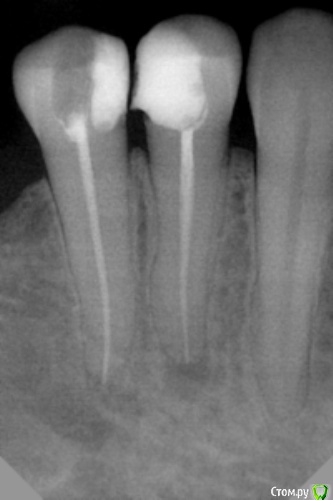

dr.Dre Опубликовано 18 августа, 2015 Поделиться Опубликовано 18 августа, 2015 Добрый день,пациентка 30 лет,жалобы на ночные боли 45 зубе,запломбировал канал ноет уже неделю,назначал НВПС,не помогло,говорит зуб реагирует на холодное.На 44 разрежение костной ткани может ето он? Ссылка на комментарий

Ker Опубликовано 18 августа, 2015 Поделиться Опубликовано 18 августа, 2015 (изменено) Больше претендентов на пульпит\кариес нет?44 давно лечен?Причина точно в 45? Апикальная часть парочки выглядит сомнительно Изменено 18 августа, 2015 пользователем Ker 1 Ссылка на комментарий

Паращук Роман Опубликовано 18 августа, 2015 Поделиться Опубликовано 18 августа, 2015 Недостаточная мех обработка корневых каналов,неясен протокол ирригации. Может поп канал в 44. http://s019.radikal.ru/i616/1508/91/c1609413d3a1.jpg Ссылка на комментарий

dr.Dre Опубликовано 18 августа, 2015 Автор Поделиться Опубликовано 18 августа, 2015 Недостаточная мех обработка корневых каналов,неясен протокол ирригации. Может поп канал в 44. http://s019.radikal.ru/i616/1508/91/c1609413d3a1.jpgконечная обработка 35/4,ирригация Гипохлорит,конечная хлоргексидин 0,05%,канал сушил спиртом Ссылка на комментарий

Бардо Опубликовано 18 августа, 2015 Поделиться Опубликовано 18 августа, 2015 (изменено) конечная обработка 35/4 блин, 35.04 он на снимке не так выглядит. Что-то у вам или с синструментацией или с обтурацией. Это у вас один штифт в канале, да? Изменено 18 августа, 2015 пользователем Бардо 3 Ссылка на комментарий

sydnik Опубликовано 18 августа, 2015 Поделиться Опубликовано 18 августа, 2015 (изменено) да там один штифт в канале, а вокруг куча г...и зачем вам эта вода (хлоргесидин 0.05%) Изменено 18 августа, 2015 пользователем sydnik Ссылка на комментарий

dr.Dre Опубликовано 19 августа, 2015 Автор Поделиться Опубликовано 19 августа, 2015 блин, 35.04 он на снимке не так выглядит. Что-то у вам или с синструментацией или с обтурацией. Это у вас один штифт в канале, да?штифт один,метод центрального штифта,латеральной конденсацией не владею Ссылка на комментарий